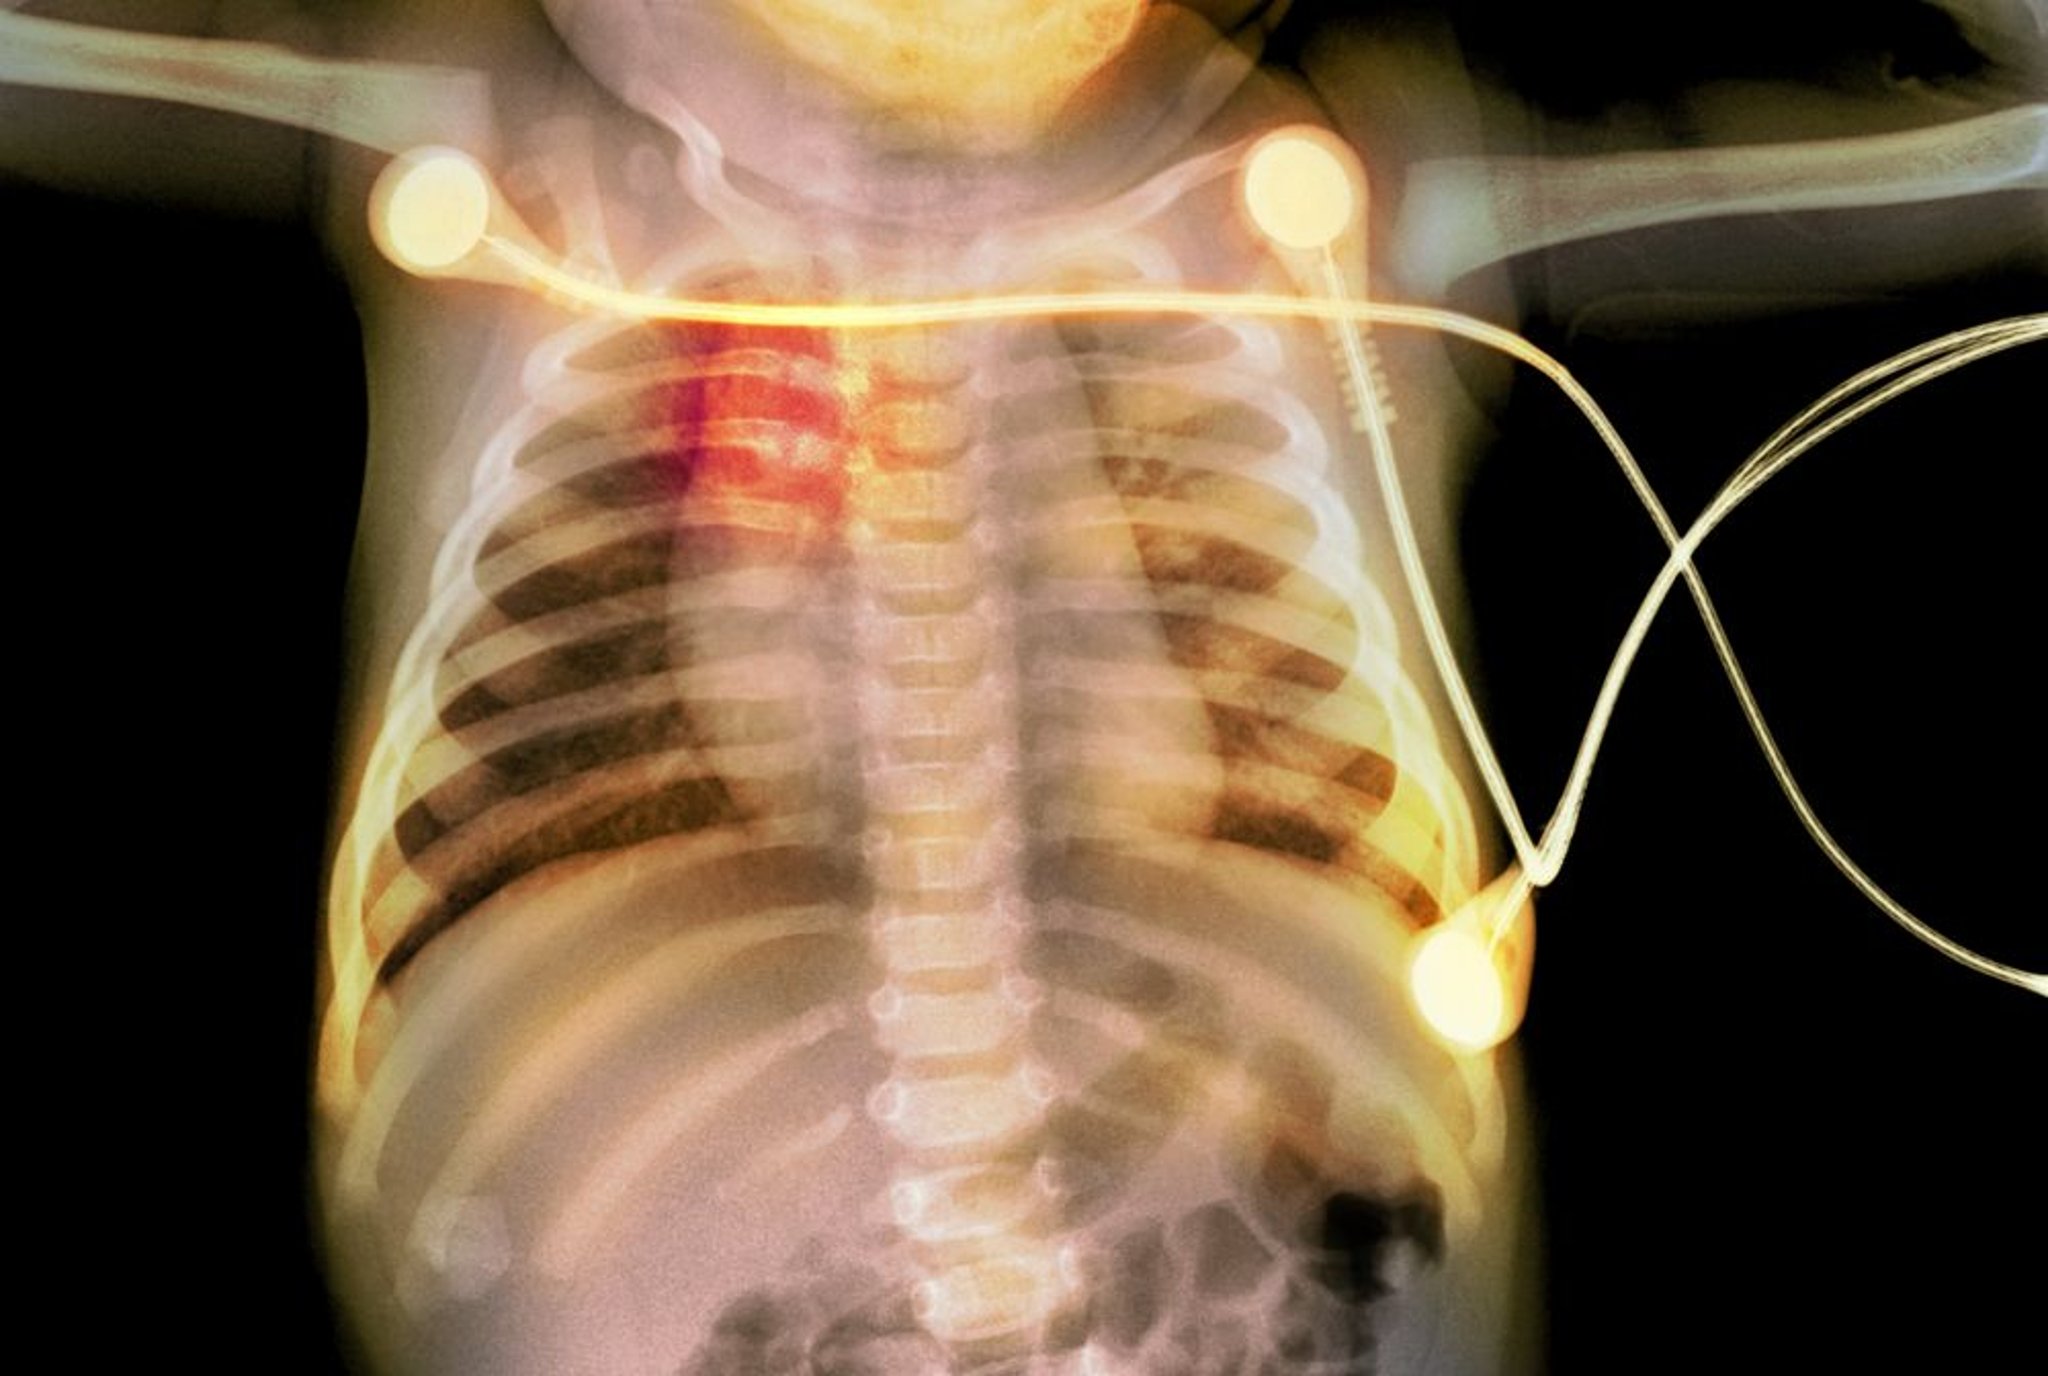

Rib Fractures in an Infant

This radiograph shows rib fractures (highlighted in red) in an infant, suggestive of child abuse.